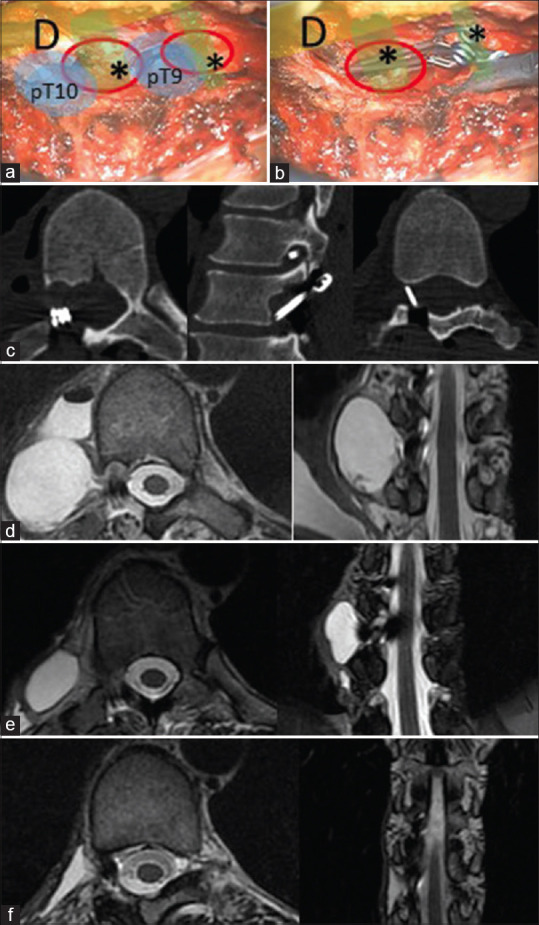

Subarachnoid-pleural fistula (SPF), a rare complication following transthoracic spinal surgery, results in the accumulation of cerebrospinal fluid (CSF) in the pleural space. Hindered spontaneous closure, attributed to negative pleural pressure, gives rise to CSF hypotension and subdural blood collections. Despite numerous reported cases, achieving consensus on management remains elusive. Treatment options encompass conservative measures, surgical repair, epidural blood patch, and diverse approaches such as multilayer dural closure or meningocele resection. Presented herein is a distinctive case following lateral thoracic meningocele surgery, where SPF-induced CSF hypotension found successful resolution through the innovative use of titanium hemostatic clips to occlude the meningocele. This novel approach, emphasizing the utility of titanium clips, deviates from conventional strategies. Surgical SPF exclusion, particularly leveraging titanium clips, emerges as a potential solution, effectively alleviating symptoms of CSF hypotension. The article also aims to present a personal experience, contributing an effective and alternative approach for the etiological treatment of thoracic meningocele.